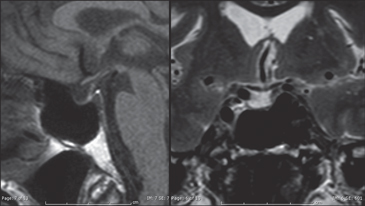

El TAC de cerebro y silla turca mostró una silla turca pequeña, con contenido hipodenso, lo cual podría corresponder a silla turca parcialmente vacía. RM: silla turca de tamaño reducido, tejido hipofisiario reducido al piso de la cavidad selar, aracnoidocele secundario (Figura 2).

Figura 2. Resonancia Magnética de silla turca. RM que

muestra ausencia de adenohipófisis en T1 (izquierda) y

aracnoidocele en T2 (derechaAl interrogatorio dirigido la paciente refirió el antecedente de hemorragia uterina en su último parto (1977) que requirió histerectomía de urgencia, quedando en agalactia; desde mediados de 1990 inicia astenia, adinamia, intolerancia al frío, fatigabilidad y episodios autolimitados de diarreas, manifestaciones todas progresivas en el tiempo.